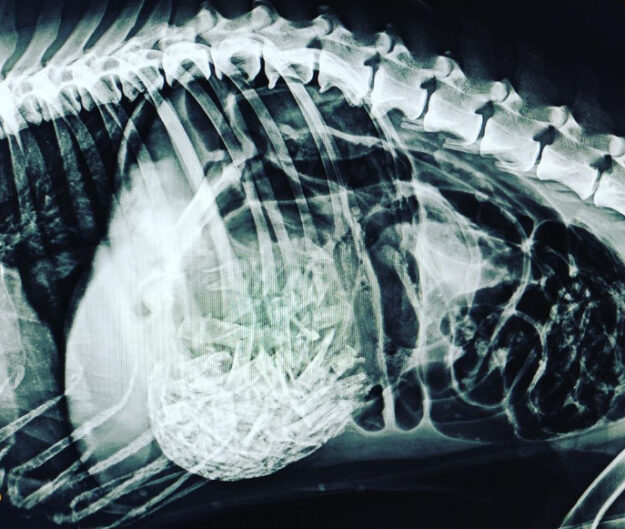

El Dick va venir d’urgències perquè no el veien bé. Tenia molt dolor abdominal i li vam fer una radiografia. En aquest cas, la imatge ens va donar un diagnòstic! Li vam diagnosticar una torsió d’estòmac degut a la ingesta d’ossos de pollastre. L’única manera per poder-li salvar la vida al Dick era sotmetre’l a…